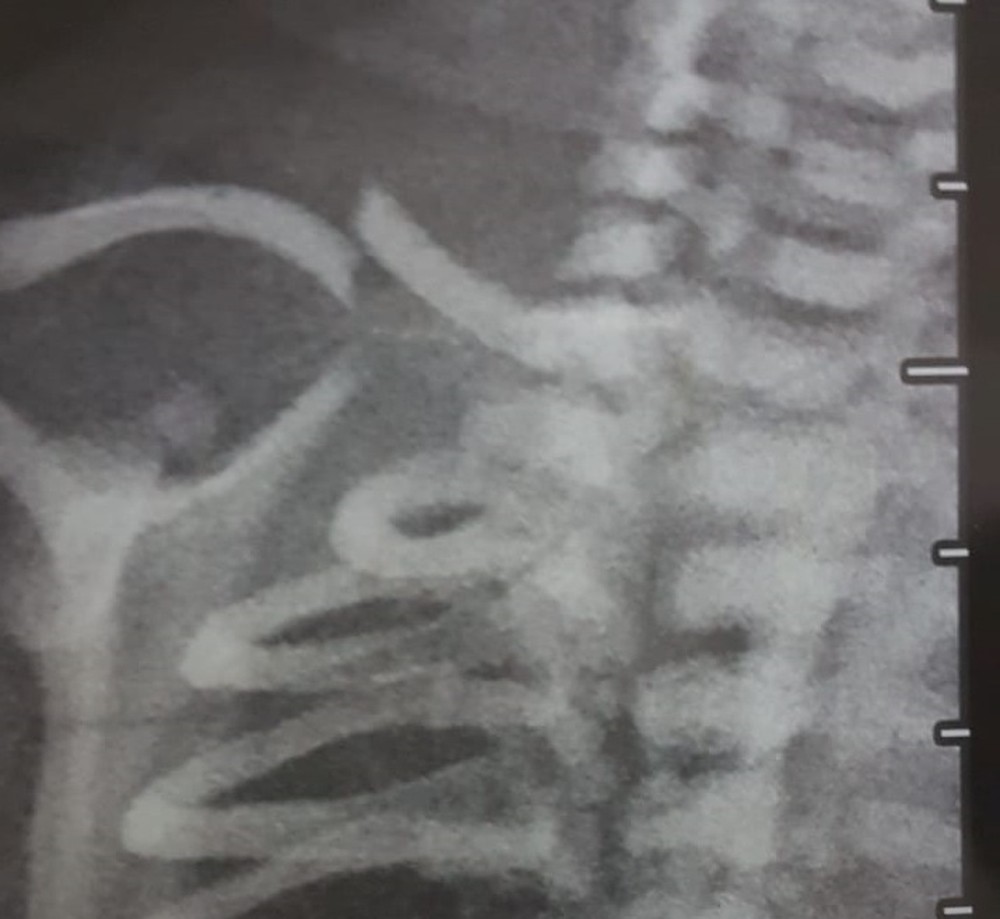

Em imagem de raio-x, é possível ver osso da criança fraturado. G1 revelou investigação sobre casos de negligência médica e violência obstétrica no HRSam.

Arquivo Pessoal

Bruna afirma que, após o parto, o filho só chorava. "Ninguém podia encostar nele, eu não sabia o que estava acontecendo", afirma. Uma imagem do raio-x, mostra o osso da criança quebrado. Só dois dias após o nascimento do bebê, uma pediatra do hospital diagnosticou que o osso estava quebrado. Mãe e filho voltaram para casa e, após algum tempo, a fratura foi curada.

A Secretaria de Saúde afirmou que "um processo sigiloso foi aberto" para investigar as denúncias. Sobre o caso específico do recém-nascido que teve a clavícula quebrada, a pasta disse que "não irá se manifestar até a apuração de todos os fatos".